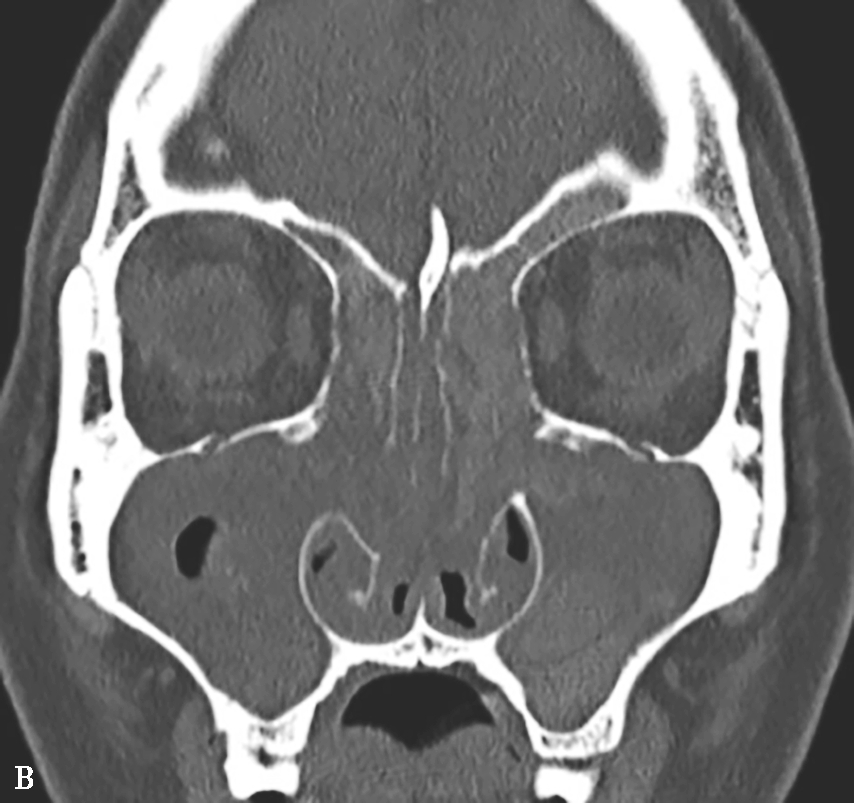

图1-3-22 变应性真菌性鼻窦炎

A、B.横断面、冠状面CT骨窗,示双侧上颌窦、筛窦腔膨胀,窦腔充填软组织密度影,病变内部可见片状磨玻璃样密度增高影,上颌窦壁骨质增生硬化;C.横断面CT软组织窗,示病变内部磨玻璃样密度影显示更清楚

①平扫表现:半组或全组窦腔内充填软组织影,骨窗示病变内部多发形态不一的云雾状或磨玻璃样密度影,CT值约100HU,软组织窗更为明显,呈不规则线状、匍匐状或斑片状高密度影(图1-3-22);常伴单或双侧鼻息肉;窦腔扩大、窦壁变薄、骨质吸收或结构不清,筛窦最常受累,眶纸板最常见骨质吸收,眶内侵犯多见。②增强扫描表现:边缘黏膜明显强化。